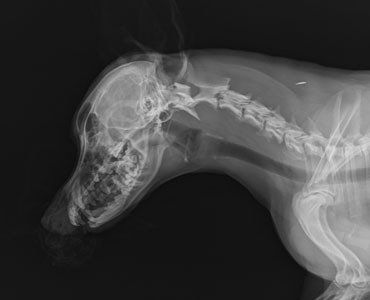

The first step in assessing a patient with a suspected orthopedic abnormality is to combine the history, signalment (breed, age, sex) and chief complaint (like right rear leg lameness). This information is combined with the orthopedic examination to both localize the problem and come up with an ordered (most likely to least likely) list of possible causes. In the majority of cases, this approach will identify the area of interest and suggest the most likely cause. The next step is choosing diagnostic tests. In most instances of lameness, radiography (x-rays) comprises the next diagnostic step.

- Digital radiography